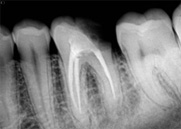

antes depois